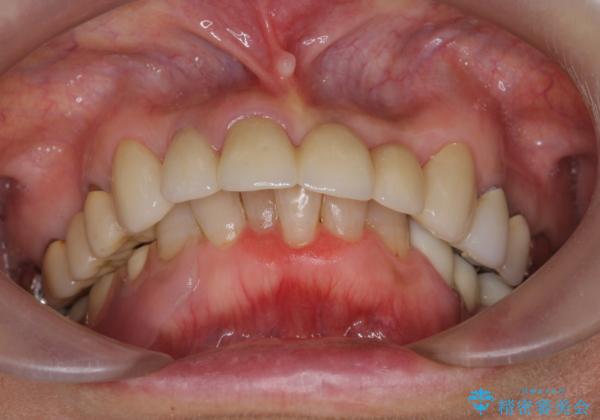

- 歩行中に躓いて転倒し、前歯2本がグラグラになってしまい痛み・審美性の改善を求めて来院されました。

X線検査・視診より強くぶつけた前歯は折れてしまい、抜歯が必要な状況です。

抜歯後の見た目改善として深い咬合関係であることからインプラントは避け、ブリッジで補綴治療を行っていくこととしました。

元々の噛み合わせが深く(ディープバイト)、転んで顎を強打したことで上顎前歯2本が根元から折れてしまい抜歯をしなければいけない状況となってしまいました。

今後前歯への負担を減らすためにナイトガードマウスピースを使用していただき歯の保存に努めていきます。